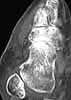

58 y/o female, had ankle sprain 3 months ago. First avulsion fracture on the tip of fibula was diagnosed and cast was applied for four weeks. After cast removal pain and swelling did not subside.

Now has mild swelling at ankle. Walks with cruches, weight bearing is not possible due to pain.

I think there was a nondisplaced talar neck fracture with complicated by AVN.

Current X-ray shows sclerosis of talar body, destruction at talar dome. MRI shows diffuse swelling in talus (interesting where comes the swelling if there is avascularity?). CT does not surely confirm fracture but shows diffuse osteoporosis in tarsal bones.